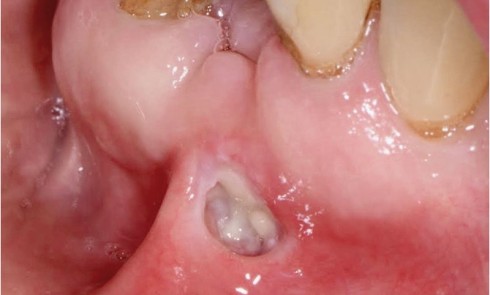

Présentation du cas clinique Un patient de 12 ans sans antécédent médical, a consulté pour des aphtes depuis 3 ans....